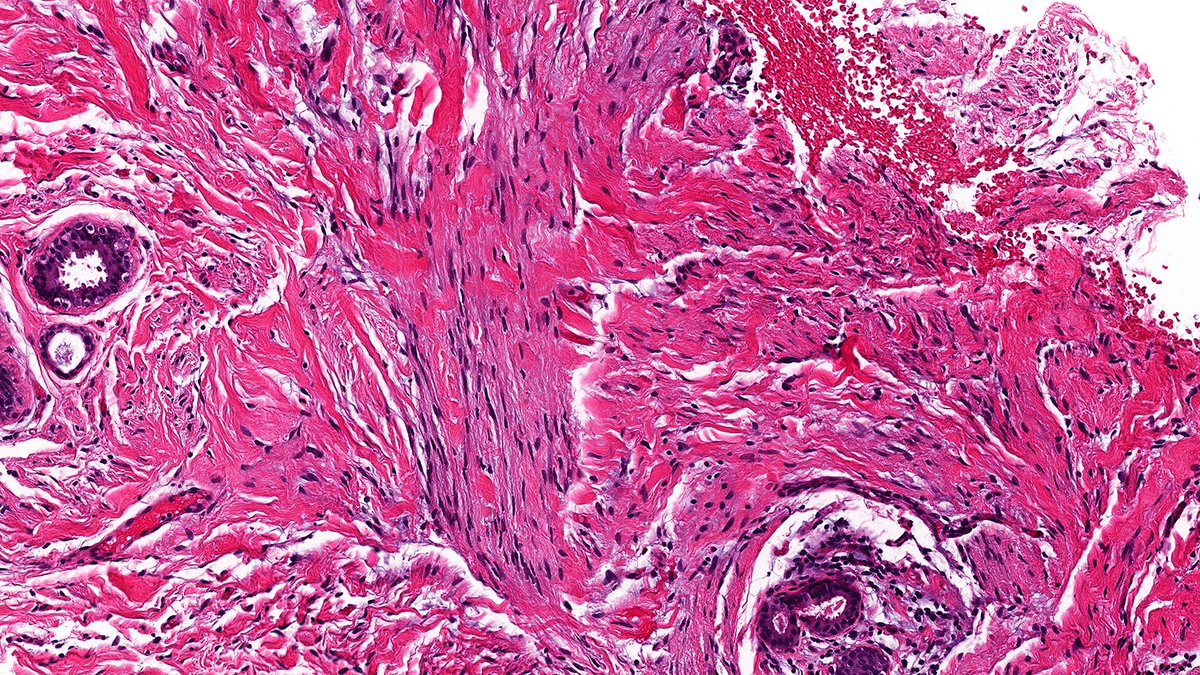

Case of Cellular Spindled Histiocytic Pseudotumor 🔬 A reactive spindle cell lesion of histiocytes — likely the exuberant end of fat necrosis — saddled with a name longer than the lesion itself. #PathX #PathTwitter #breastpath

Case of Cellular Spindled Histiocytic Pseudotumor 🔬

A reactive spindle cell lesion of histiocytes — likely the exuberant end of fat necrosis — saddled with a name longer than the lesion itself.

#PathX #PathTwitter #breastpath